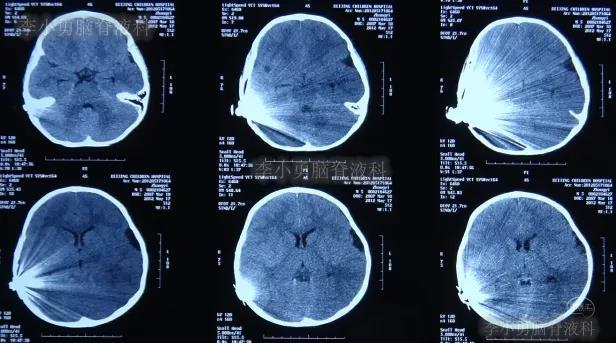

入院治疗55天即2012年8月1日,进行了脑室腹腔分流术,术后当天查脑CT示未见异常(图-11)。

图-11:2012年8月1日脑CT

2012年8月15日(外院人工耳蜗植入术后近4个月时间内:经3家三甲医院治疗后但脑积水和颅内感染仍持续加重,但李小勇脑脊液科治69天康复出院);出院时:病情好转为:开始恢复走路能力,面瘫消失(图-13);脑CT示未见异常,人工耳蜗被保留(图-14)。

图-14:2012年8月15日脑CT